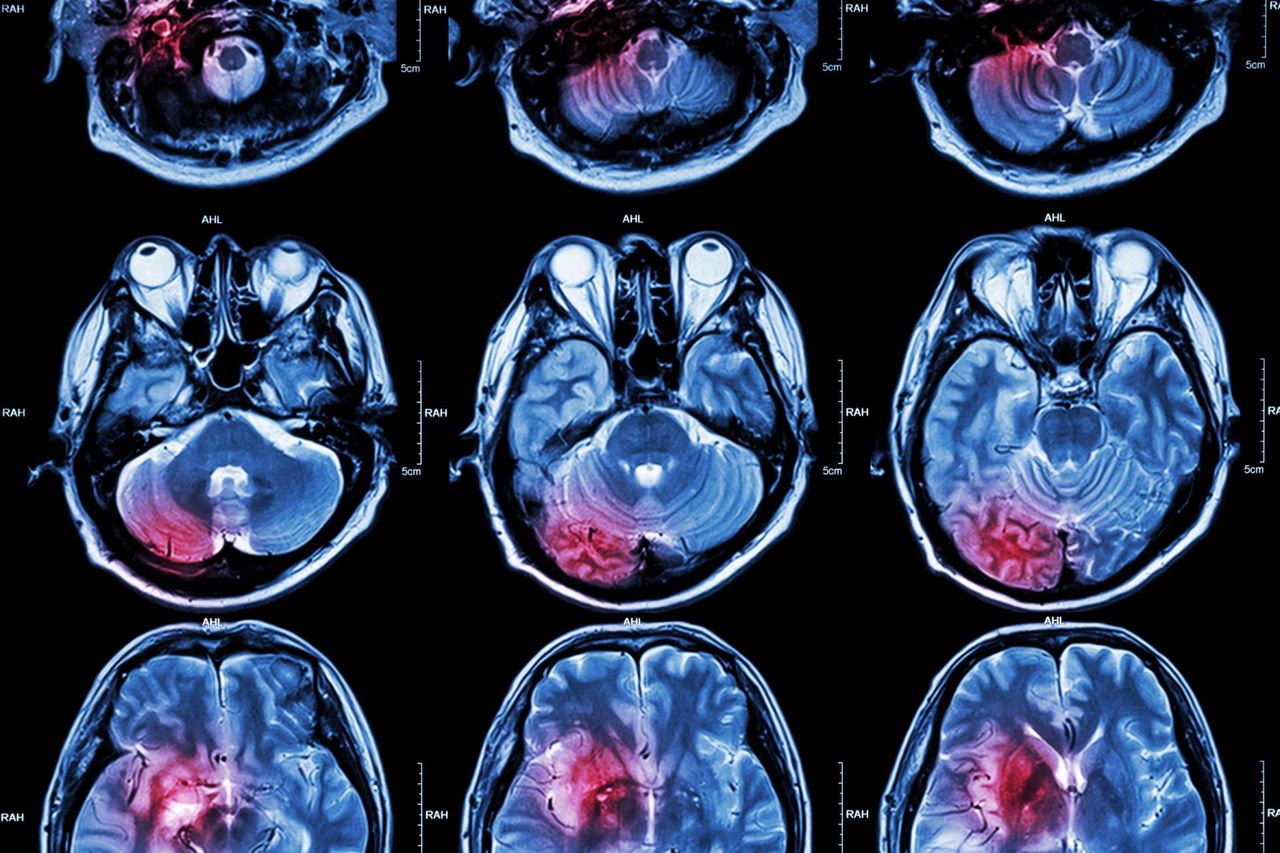

Operacja mózgu jest obarczona sporym ryzykiem. Przyczyny operacji mózgu są to poważne choroby, takie jak tętniaki, czy guzy mózgu. Obecnie operacje mózgu są stale udoskonalane, aby zwiększyć ich bezpieczeństwo.

Operacje mózgu są czasami koniecznością, gdy dochodzi do urazów głowy. Należy jednak pamiętać, że sposób leczenia zależy od rodzaju i zakresu urazu. Najczęstszą przyczyną operacji mózgu po urazach głowy jest zdiagnozowanie krwiaka. Krwiak jest poważnym zagrożeniem dla życia człowieka. Zdiagnozowany odpowiednio wcześnie, pozwala na szybkie przeprowadzenie operacji mózgu.

Gdy lekarz podejrzewa krwiaka mózgu, w pierwszej kolejności powinien wykonać tomografię komputerową. Wskazaniem do badania jest utrata przytomności, zaburzenia świadomości, zaburzenia psychiczne po urazie, obecność objawów neurologicznych, które mogą wskazywać na uszkodzenie określonego obszaru mózgu oraz pęknięcie czaszki widoczne na zdjęciu RTG.